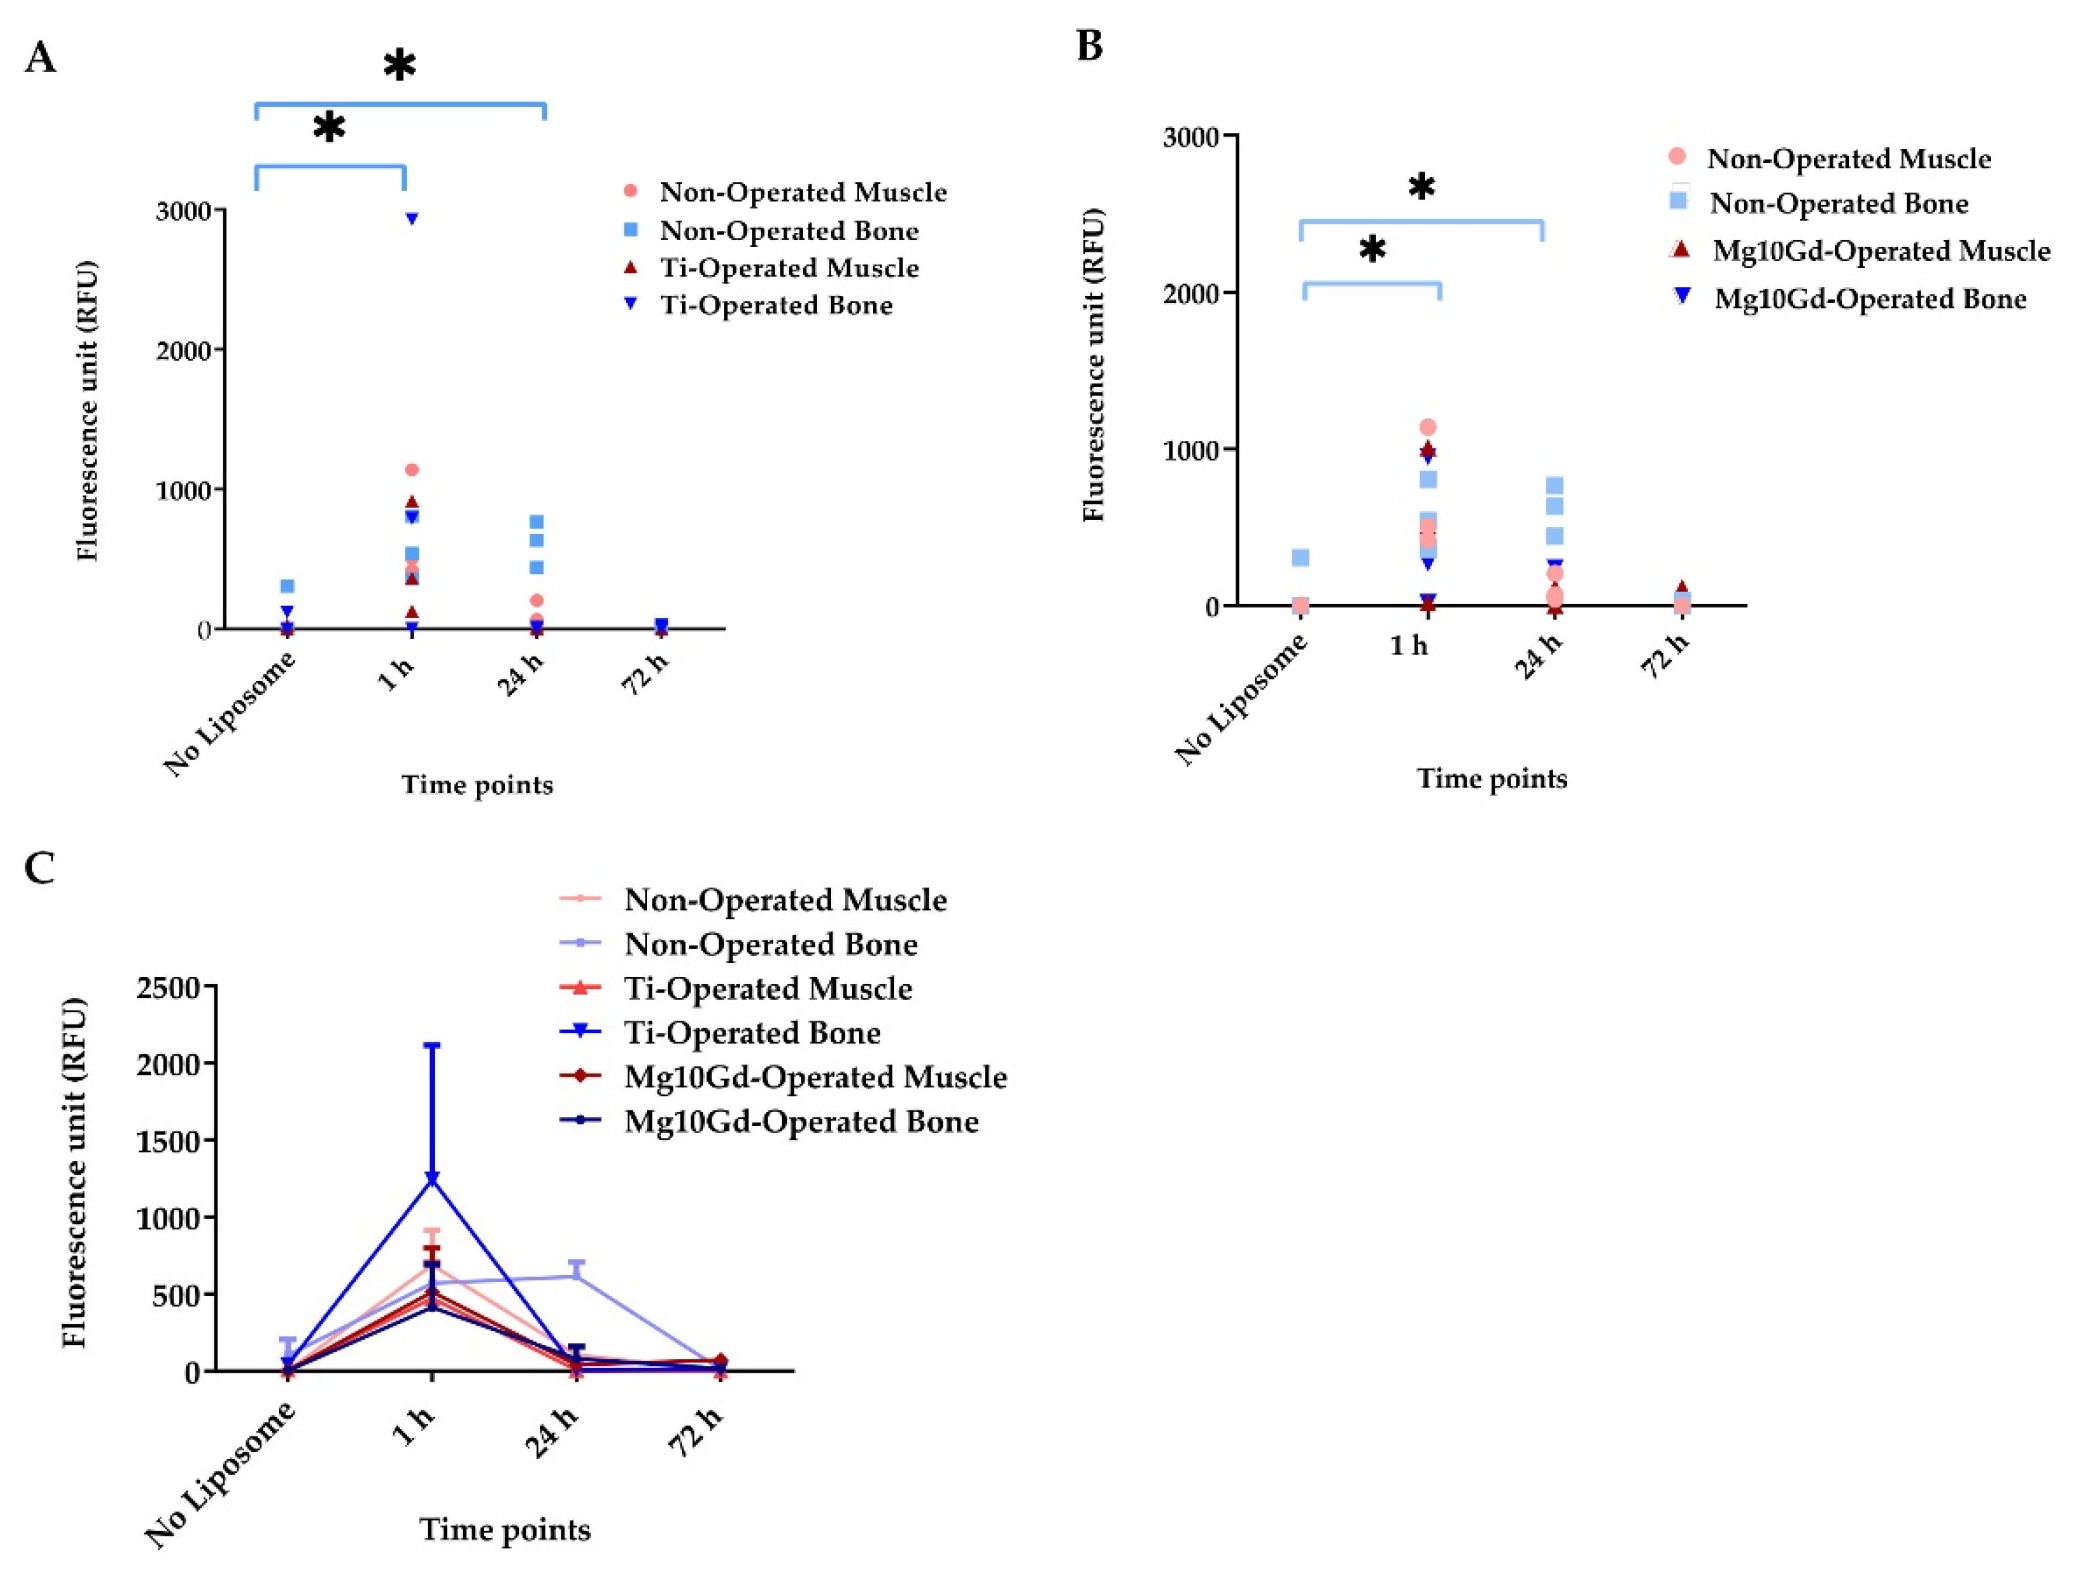

2.2. In Vivo Evaluation of α-MSH-SM-Liposomes

4.6. Imaging of α-MSH-SM-Liposomes